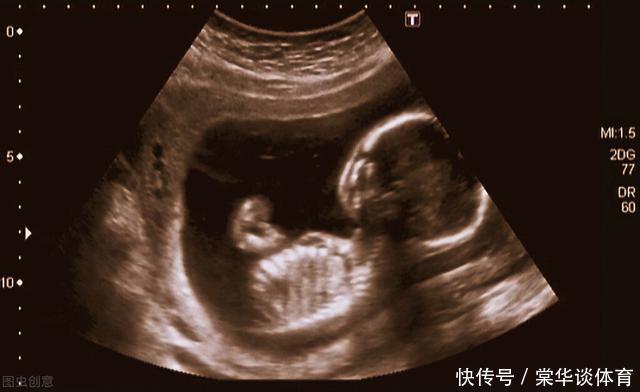

但是在做B超时,他们看到了胎儿,他已有成形的手指和脚趾,正在吮吸着自己的手指头,那个样子看起来很幸福。这“幸福的胎儿”让父亲心痛,虽然还在妈妈的肚子里,可是他们非常爱他。他们决定要救这个孩子。于是两人走遍全国,四处求医,最后他们选择了一种处于实验阶段的手术,叫宫内手术,就是在动态实时超声的引导下,给胎儿做手术。这种手术的危险不言而喻,但是克鲁斯·兰德夫妇仍然选择了它!【 手术|妻子怀孕20周,产检时被告知胎儿没有肺,夫妻俩依然决定留下这个孩子】